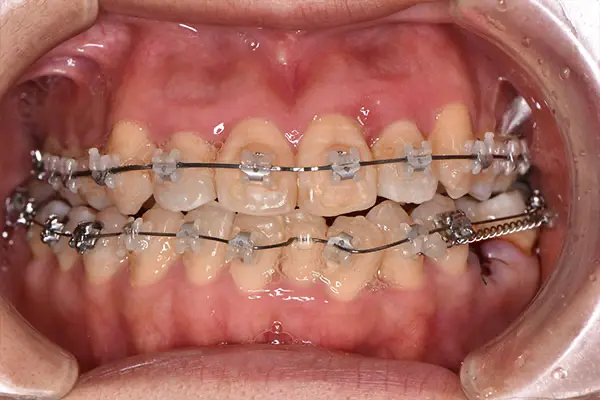

叢生・反対咬合

術前正面

術中正面

術後正面

術前上顎

| 主訴 | 歯のでこぼこ |

|---|---|

| 診断名あるいは主な症状 | 叢生、反対咬合 |

| 初診年齢 | 45歳 |

| 治療内容・装置 | マルチブラケット装置(上下表側からの矯正治療) MSE2 |

| 抜歯・非抜歯 | 下顎左第二小臼歯抜歯 |

| 治療期間 | 2年9ヶ月 |

| 費用 | 882,700円(税込) |

| 治療のリスク・副作用 | 歯の移動に伴う痛み 上下顎前歯部の歯根吸収 装置による口内炎 ブラッシング不良によるむし歯、歯周炎 |